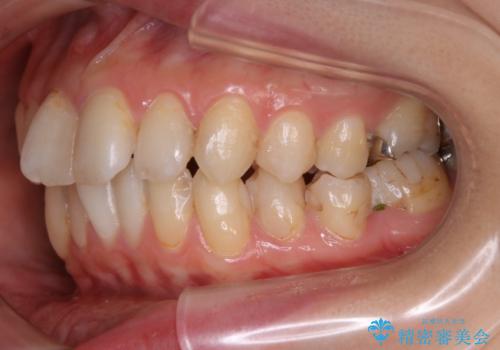

- 前歯のガタつきと噛み合わせの改善を希望してご来院されました。

目立たない装置での矯正治療をとのことでインビザラインを用いた非抜歯矯正を行うこととなりました。

虫歯の治療などが必要な部位がある場合には矯正治療に先立ち全体の状態をよくする術前治療が行われます。